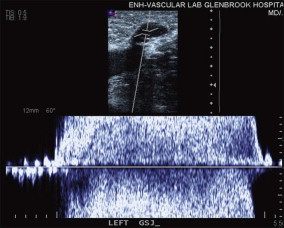

The great saphenous vein (GSV) is imaged with the patient facing the technologist and the study leg slightly forward and externally rotated. The vein is examined for dilation, compressibility, and echogenicity in the transverse orientation. The longitudinal view is also assessed, and thickness of the vein wall, valvular changes or any echogenicity are documented ( Figs 10.1–10.5 ). The operator tests for reflux in the axial vein and perforating veins using color flow, and also uses the pulsed Doppler with the probe in longitudinal orientation to test for reflux in the saphenofemoral junction, the common femoral vein above and below the saphenofemoral junction, and the proximal GSV. The Valsalva maneuver is appropriate for provoking reflux in the groin, but may not provoke reflux inferior to the groin if there is a competent valve in the groin area. Therefore, compression of the leg above and below the segment being interrogated is used to detect evidence of reflux in the target segment. For example, saphenofemoral and proximal great saphenous reflux may be masked during the Valsalva maneuver by the presence of a competent valve in the proximal common femoral vein. The author tests for this by squeezing the upper thigh between two hands (lateral and medial) while interrogating the proximal GSV with pulsed Doppler and looking for ‘to and fro’ flow. The Valsalva maneuver may also fail to demonstrate reflux in the more inferior segment of the GSV and the practitioner must depend on proximal and distal compression maneuvers to elicit reflux when it is significantly inferior to the saphenofemoral junction.

The small saphenous vein (SSV) is examined for dilation and reflux with the patient standing and facing away from the technologist and the popliteal vein is imaged from this approach as well. Examination of the SSV is started at the ankle posterior to the lateral malleolus. The course of the vein is traced proximally where it very quickly drifts to the midline of the calf and can clearly be identified within its superficial fascial compartment. Branches and connections are usually seen in the mid-calf and the operator eventually traces these branches but not until the entire course of the SSV is studied.